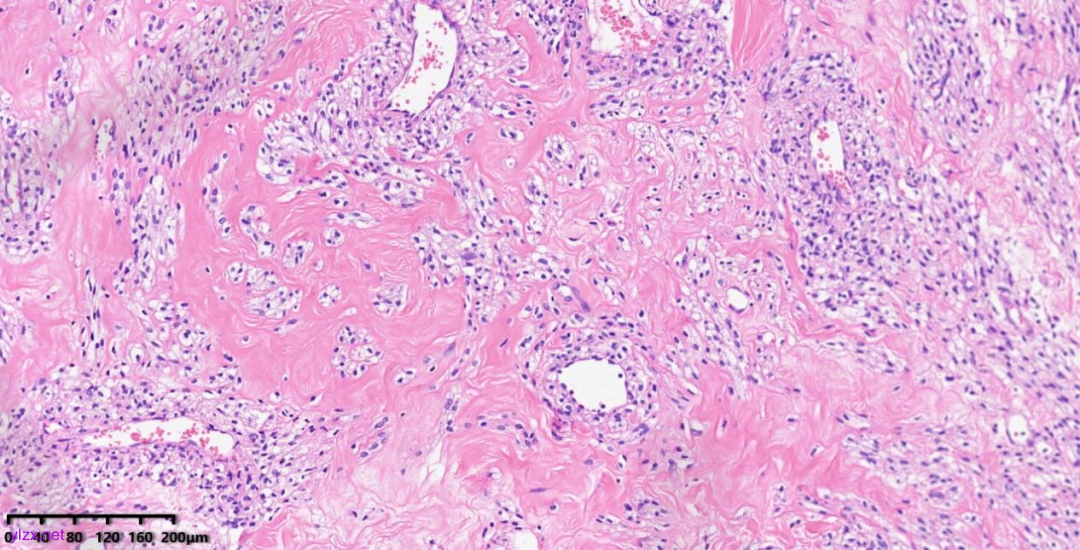

肿瘤细胞以梭形细胞、卵圆形细胞为主,部分为胞浆透亮的上皮样形态,透亮细胞界限较清,胞质淡染或胞浆丰富、嗜酸性,肿瘤内血管丰富,肿瘤细胞围绕血管周围片巢状、束状及放射状排列;肿瘤细胞核异型性不明显,核分裂像少见(<1个/50HPF),染色质开放,可见小核仁;肿瘤间质水肿、黏液变性,纤维胶原增生伴玻璃样变性。

图1~5 低倍镜下:肿瘤细胞以梭形细胞、卵圆形细胞为主,部分为胞浆透亮的上皮样形态,肿瘤细胞分布疏密不均,部分区密集丰富,部分区肿瘤细胞稀少,间质疏松水肿、黏液变性,肿瘤细胞围绕血管周围生长,局部间质纤维胶原增生伴玻璃样变性。

图6 中倍镜下:肿瘤内血管丰富,胞浆透亮的上皮样细胞围绕血管周围片巢状、束状及放射状排列。

图7~10 高倍镜下:梭形细胞、上皮样细胞组成的巢状、梁状结构,周围包绕纤细的薄壁毛细血管,肿瘤细胞呈放射状排列在血管周围,细胞界限较清,胞浆丰富、嗜酸性或透亮,细胞异型性不明显,核分裂像少见,细胞核呈圆形,染色质开放,可见小核仁;局部少量慢性炎细胞浸润。